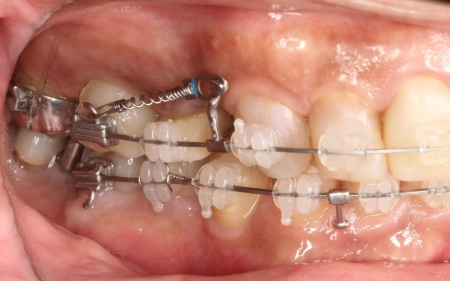

その後、ワイヤー矯正とクローズドコイル(バネの装置)を使ったスピード矯正を行い、前歯を後方に移動させます。

下顎は残根も利用しながら、矯正用の小さなネジ「テンポラリーインプラント(インプラントアンカー)」を顎の骨に埋め込んで固定源とする方法も併用し、歯を移動させました。

矯正期間中は定期的に装置の調整を行い、歯の動きや噛み合わせの変化を確認しながら治療を進めています。